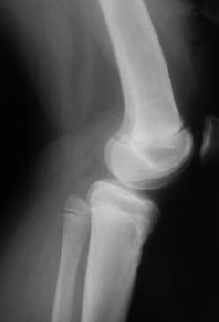

Рис. 2. 2,5 года после травмы

Рис. 3. 3,5 года после травмы

Рис. 4. Вид конечности при вертикальной нагрузке

В связи с наличием функционального и косметического дефекта было принято решение об оперативной коррекции (рис. 5, 6). Ребенку была выполнена остеотомия большеберцовой кости в в/3, осуществлено наложение комбинированного аппарата внешней фиксации с дальнейшей коррекцией оси и укорочения по Г.А. Илизарову (рис. 7).